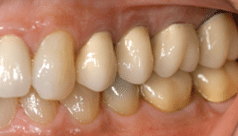

Fig. 1: Hand-Crafted Dental Crown Demonstrating Precision Fabrication

Why is it that our crowns last for such a long time? Attention to detail with the tooth preparation and temporization, taking the clinical or digital impression, and the fabrication in our in-house laboratory are key to obtaining precision results. Our technician hand-crafts each crown and evaluates the precision of the fit. Finally, all crowns are X-rayed to ensure that the anticipated crown fit has been achieved. If not, we simply redo the crown. It must be perfect.

This commitment to precision goes beyond what standard milling machines can achieve. When you partner with Dr. Marlin and our team, you’re investing in craftsmanship that is backed by decades of experience. Each crown is created with the understanding that it will be part of your smile for decades to come, not just a few years.